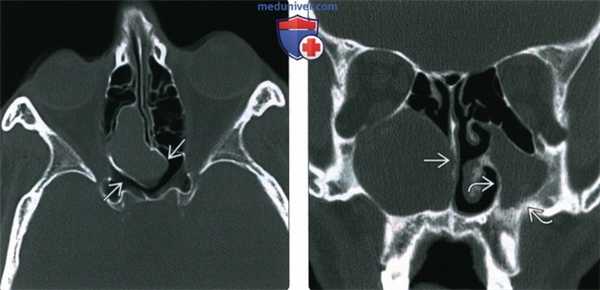

(Слева) При аксиальной «костной» КТ визуализируется заднее решетчатое мукоцеле, пролабирующее в основные пазухи, но не в орбиту. Определяется истончение и ремоделирование костей вокруг мукоцеле.

(Справа) При корональной «костной» КТ визуализируется крупное мукоцеле в правой верхнечелюстной пазухе (нетипичная локализация). Мукоцеле блокирует полость носа. Оцените изменения, обусловленные хроническим левосторонним гайморитом, - снижение объема пазухи и истончение стенок.

(Слева) На аксиальной КТ в костном окне определяется мукоцеле задних ячеек решетчатой пазухи, распространяющееся в сфеноидальные пазухи, но не в глазницу. Костная пластинка на периферии мукоцеле истончена и видоизменена.

(Справа) На корональной КТ в костном окне в правой верхнечелюстной пазухе (нетипичная локализация) определяется мукоцеле большого размера, приводящее к обструкции полоаи носа. Обратите внимание на признаки хронического левоаороннего гайморита: уменьшение объема пазухи и утолщение ее стенок.